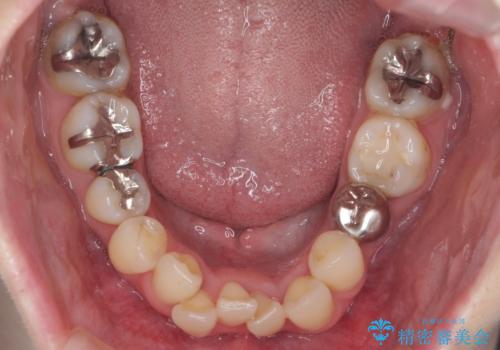

- 八重歯を主訴に来院。他院で全体ワイヤー矯正、4本抜歯で3-4年かかるかもしれないと説明を受けたとのこと。

八重歯の部分は抜歯し、奥に入っていた前歯を前に移動させました。

下の前歯は生まれつき3本だったため、さらに2本下を抜くとなると3本少なくなってしまうため、下の前歯を一本お取りして最小限の抜歯としました。

上にはワイヤー部分矯正を行った後、インビザラインでマウスピース矯正を行っています。